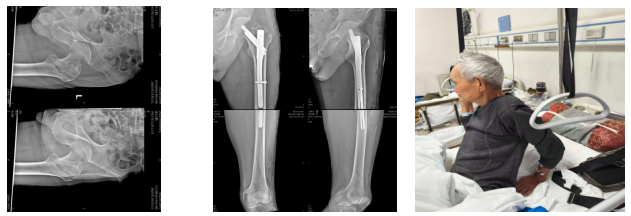

患者3:73岁的夏奶奶,既往有冠心病病史,双肺肺气肿,未规律治疗,因摔伤致右侧股骨颈骨折,患者心脏、肺功能欠佳,围手术期极易发生心脏骤停,肺部感染等并发症。

术前: 术后: